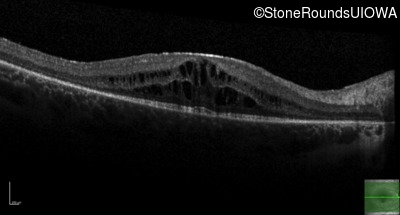

Optical Coherence Tomography - Right - 20/32 -1

Exemplar / OCT Stack

OCT Stack